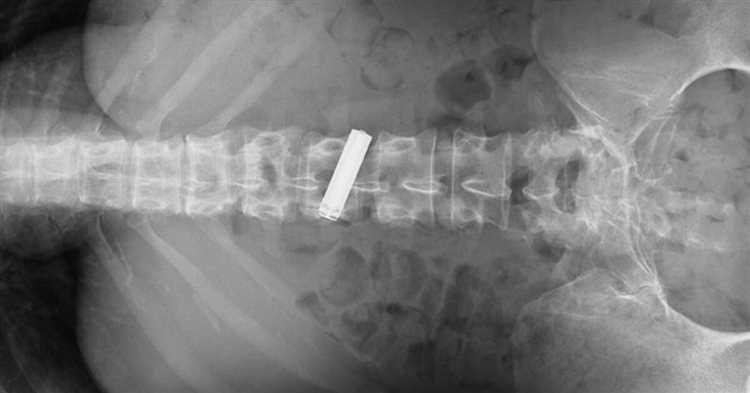

Если батарейка застревает в пищеводе или желудке, она может вызвать химическое обожжение слизистой оболочки, что может привести к язвам и болезненным ощущениям. Батарейка также может повредить или перфорировать стенку органа, вызывая кровотечение и инфекцию.